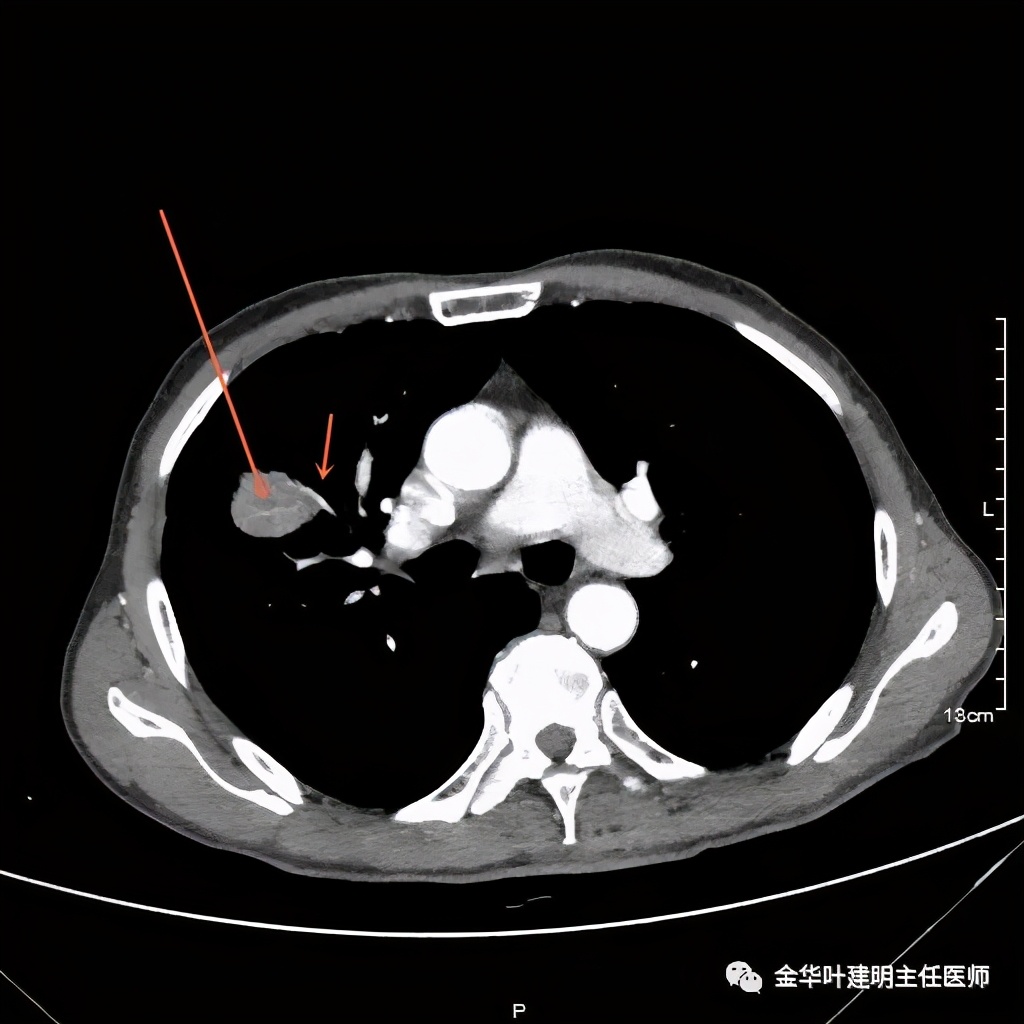

金华的某A,今年73岁,男性。检查发现右上肺占位,肿瘤筛查指标正常,血常规与CRP正常,临床有反复咳嗽、咳痰2年余(考虑慢支的关系,近期也许同时有病灶的影响)。一年前还在外院做过支气管镜,也未见确切异常。我们先来看他这次的胸部CT图像:

上图示病灶

上图示纵隔窗实性